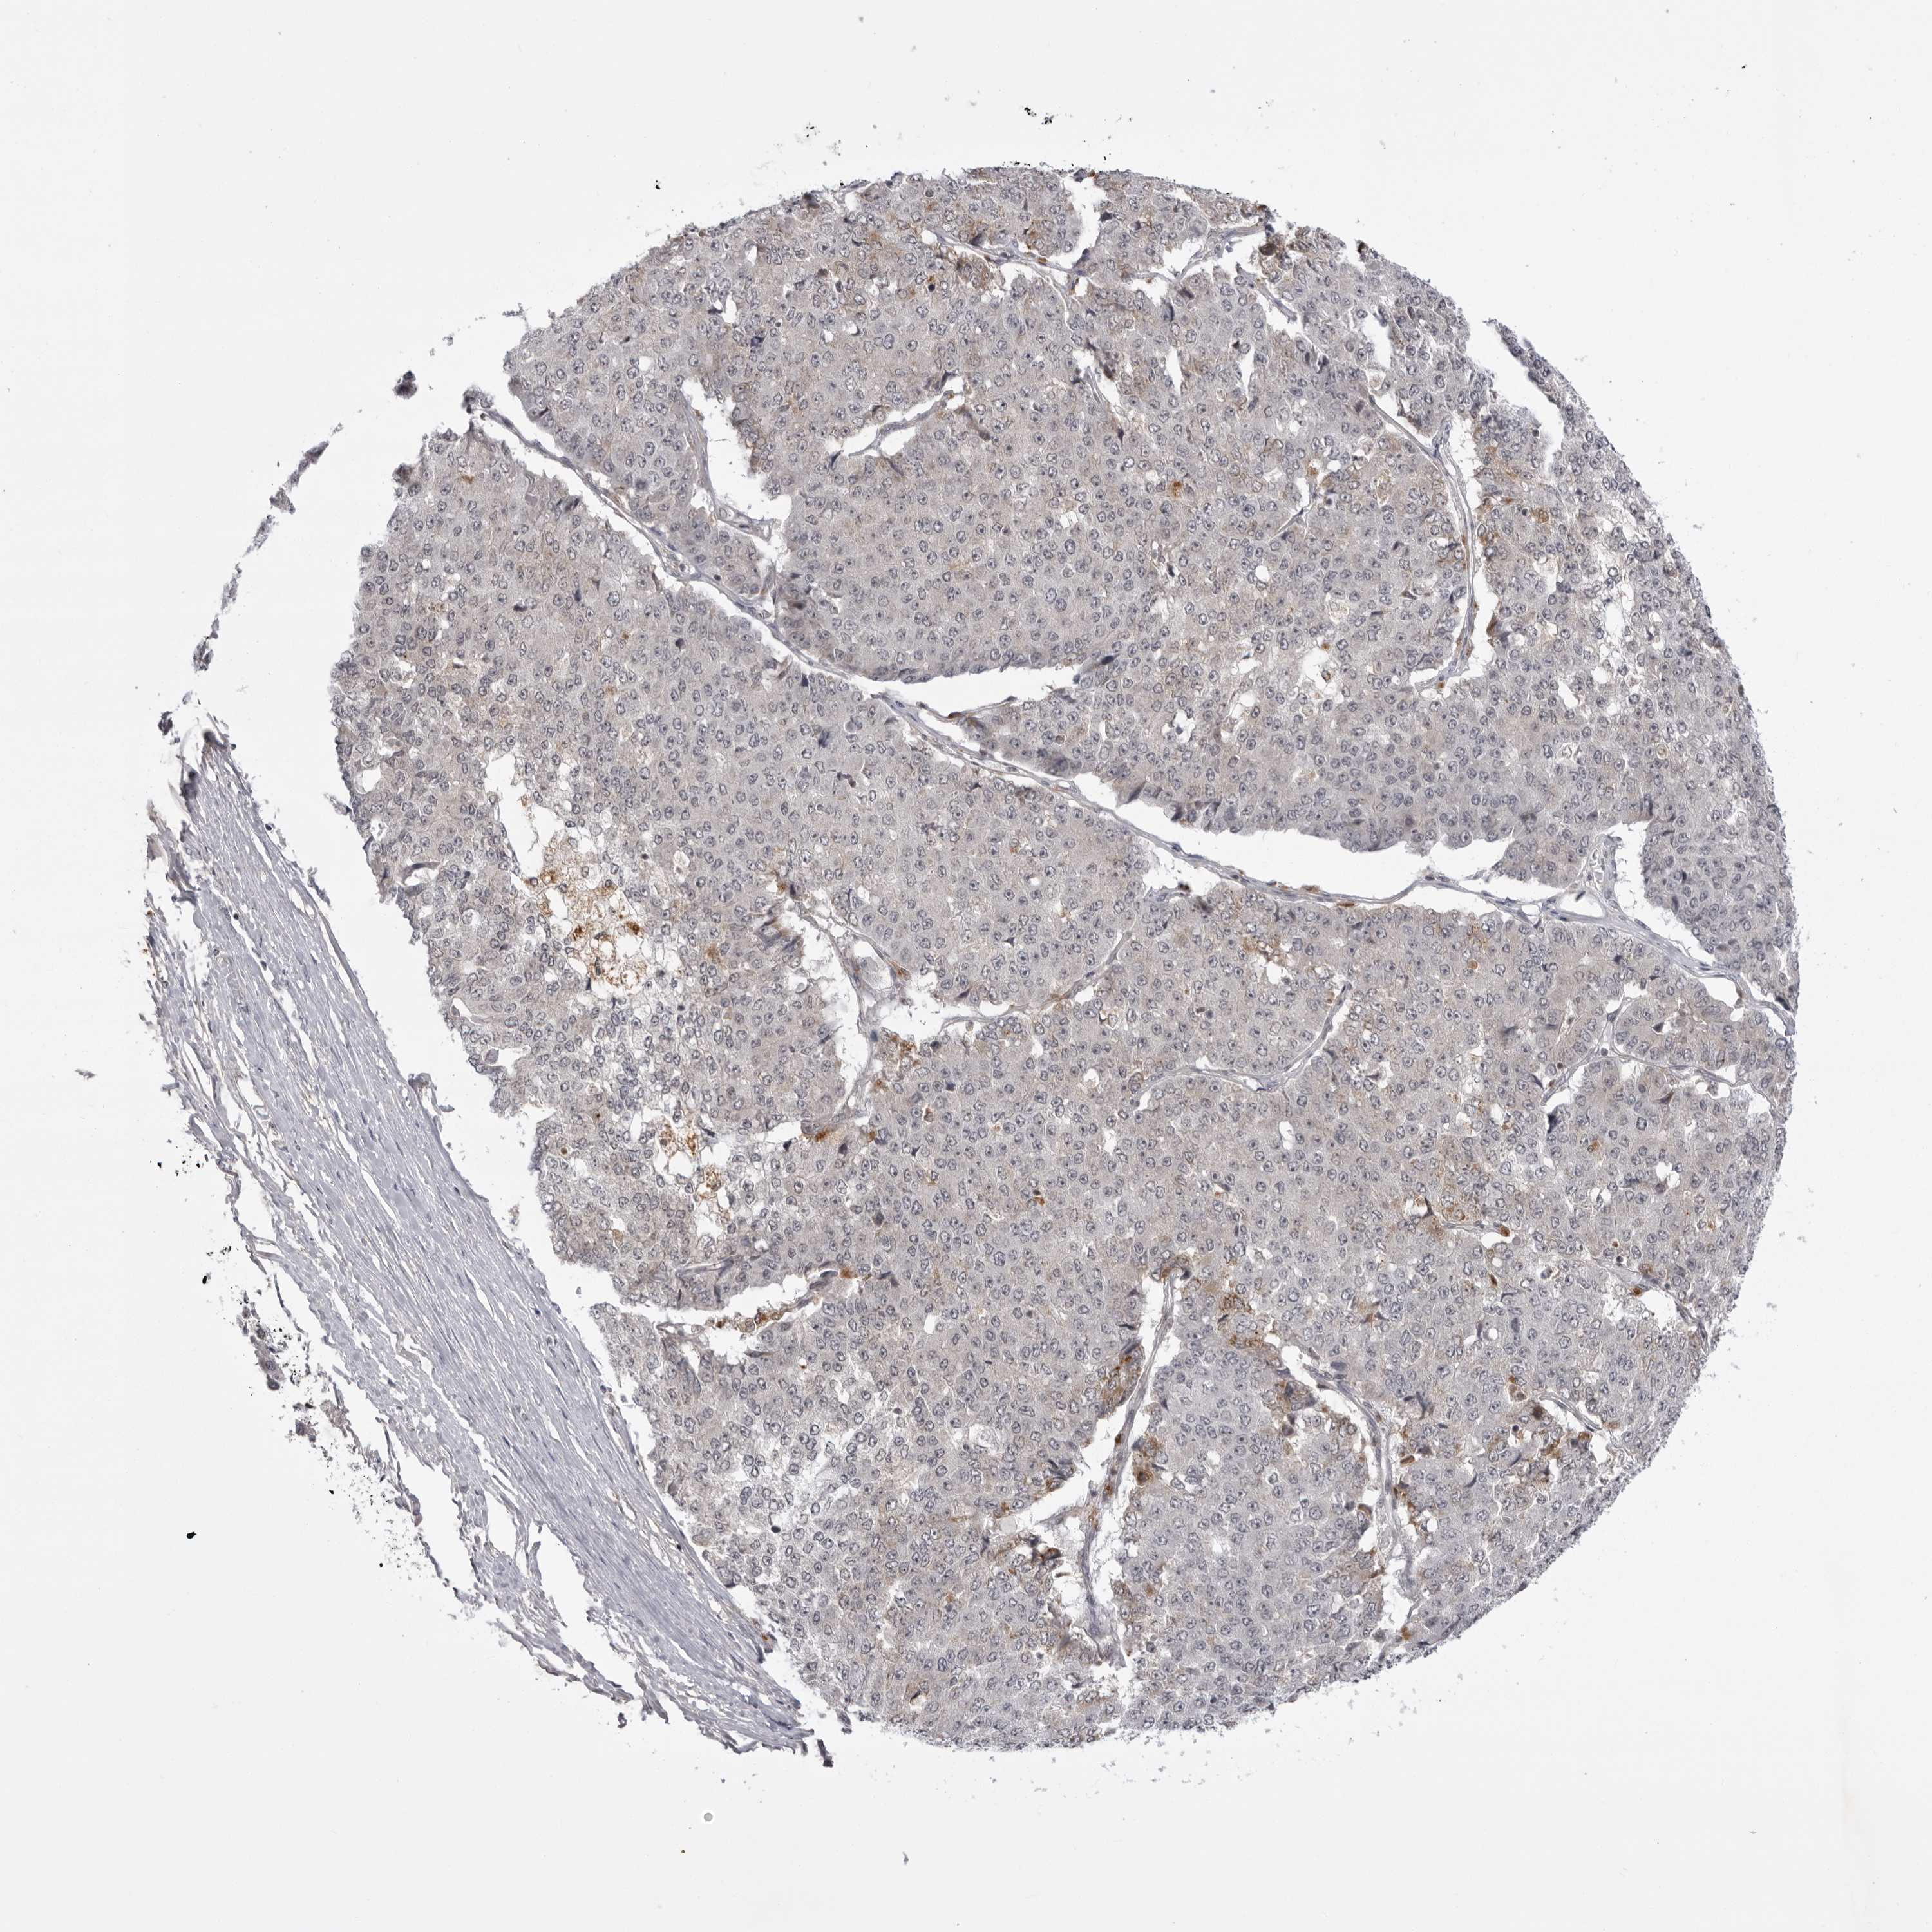

PANCREATIC CANCER - Protein expressioni

A mouse-over function shows sample information and annotation data. Click on an image to view it in a full screen mode. Samples can be filtered based on level of antibody staining by selecting one or several of the following categories: high, medium, low and not detected. The assay and annotation is described here.

Note that samples used for immunohistochemistry by the Human Protein Atlas do not correspond to samples in the TCGA dataset.

Antibody stainingi

Antibody staining in the annotated cell types in the current human tissue is reported as not detected, low, medium, or high, based on conventional immunohistochemistry profiling in selected tissues. This score is based on the combination of the staining intensity and fraction of stained cells.

Each image is clickable and will lead to virtual microscopy that enables deeper exploration of all samples and also displays staining intensity scores, fraction scores and subcellular localization as well as patient and tissue information for each sample.

Antibody HPA023389

Antibody HPA027762

Staining

High

Medium

Low

Not detected

Intensity

Strong

Moderate

Weak

Negative

Quantity

>75%

75%-25%

<25%

None

Location

Nuclear

Cytoplasmic/membranous

Cytoplasmic/membranous,nuclear

Adenocarcinoma, NOS